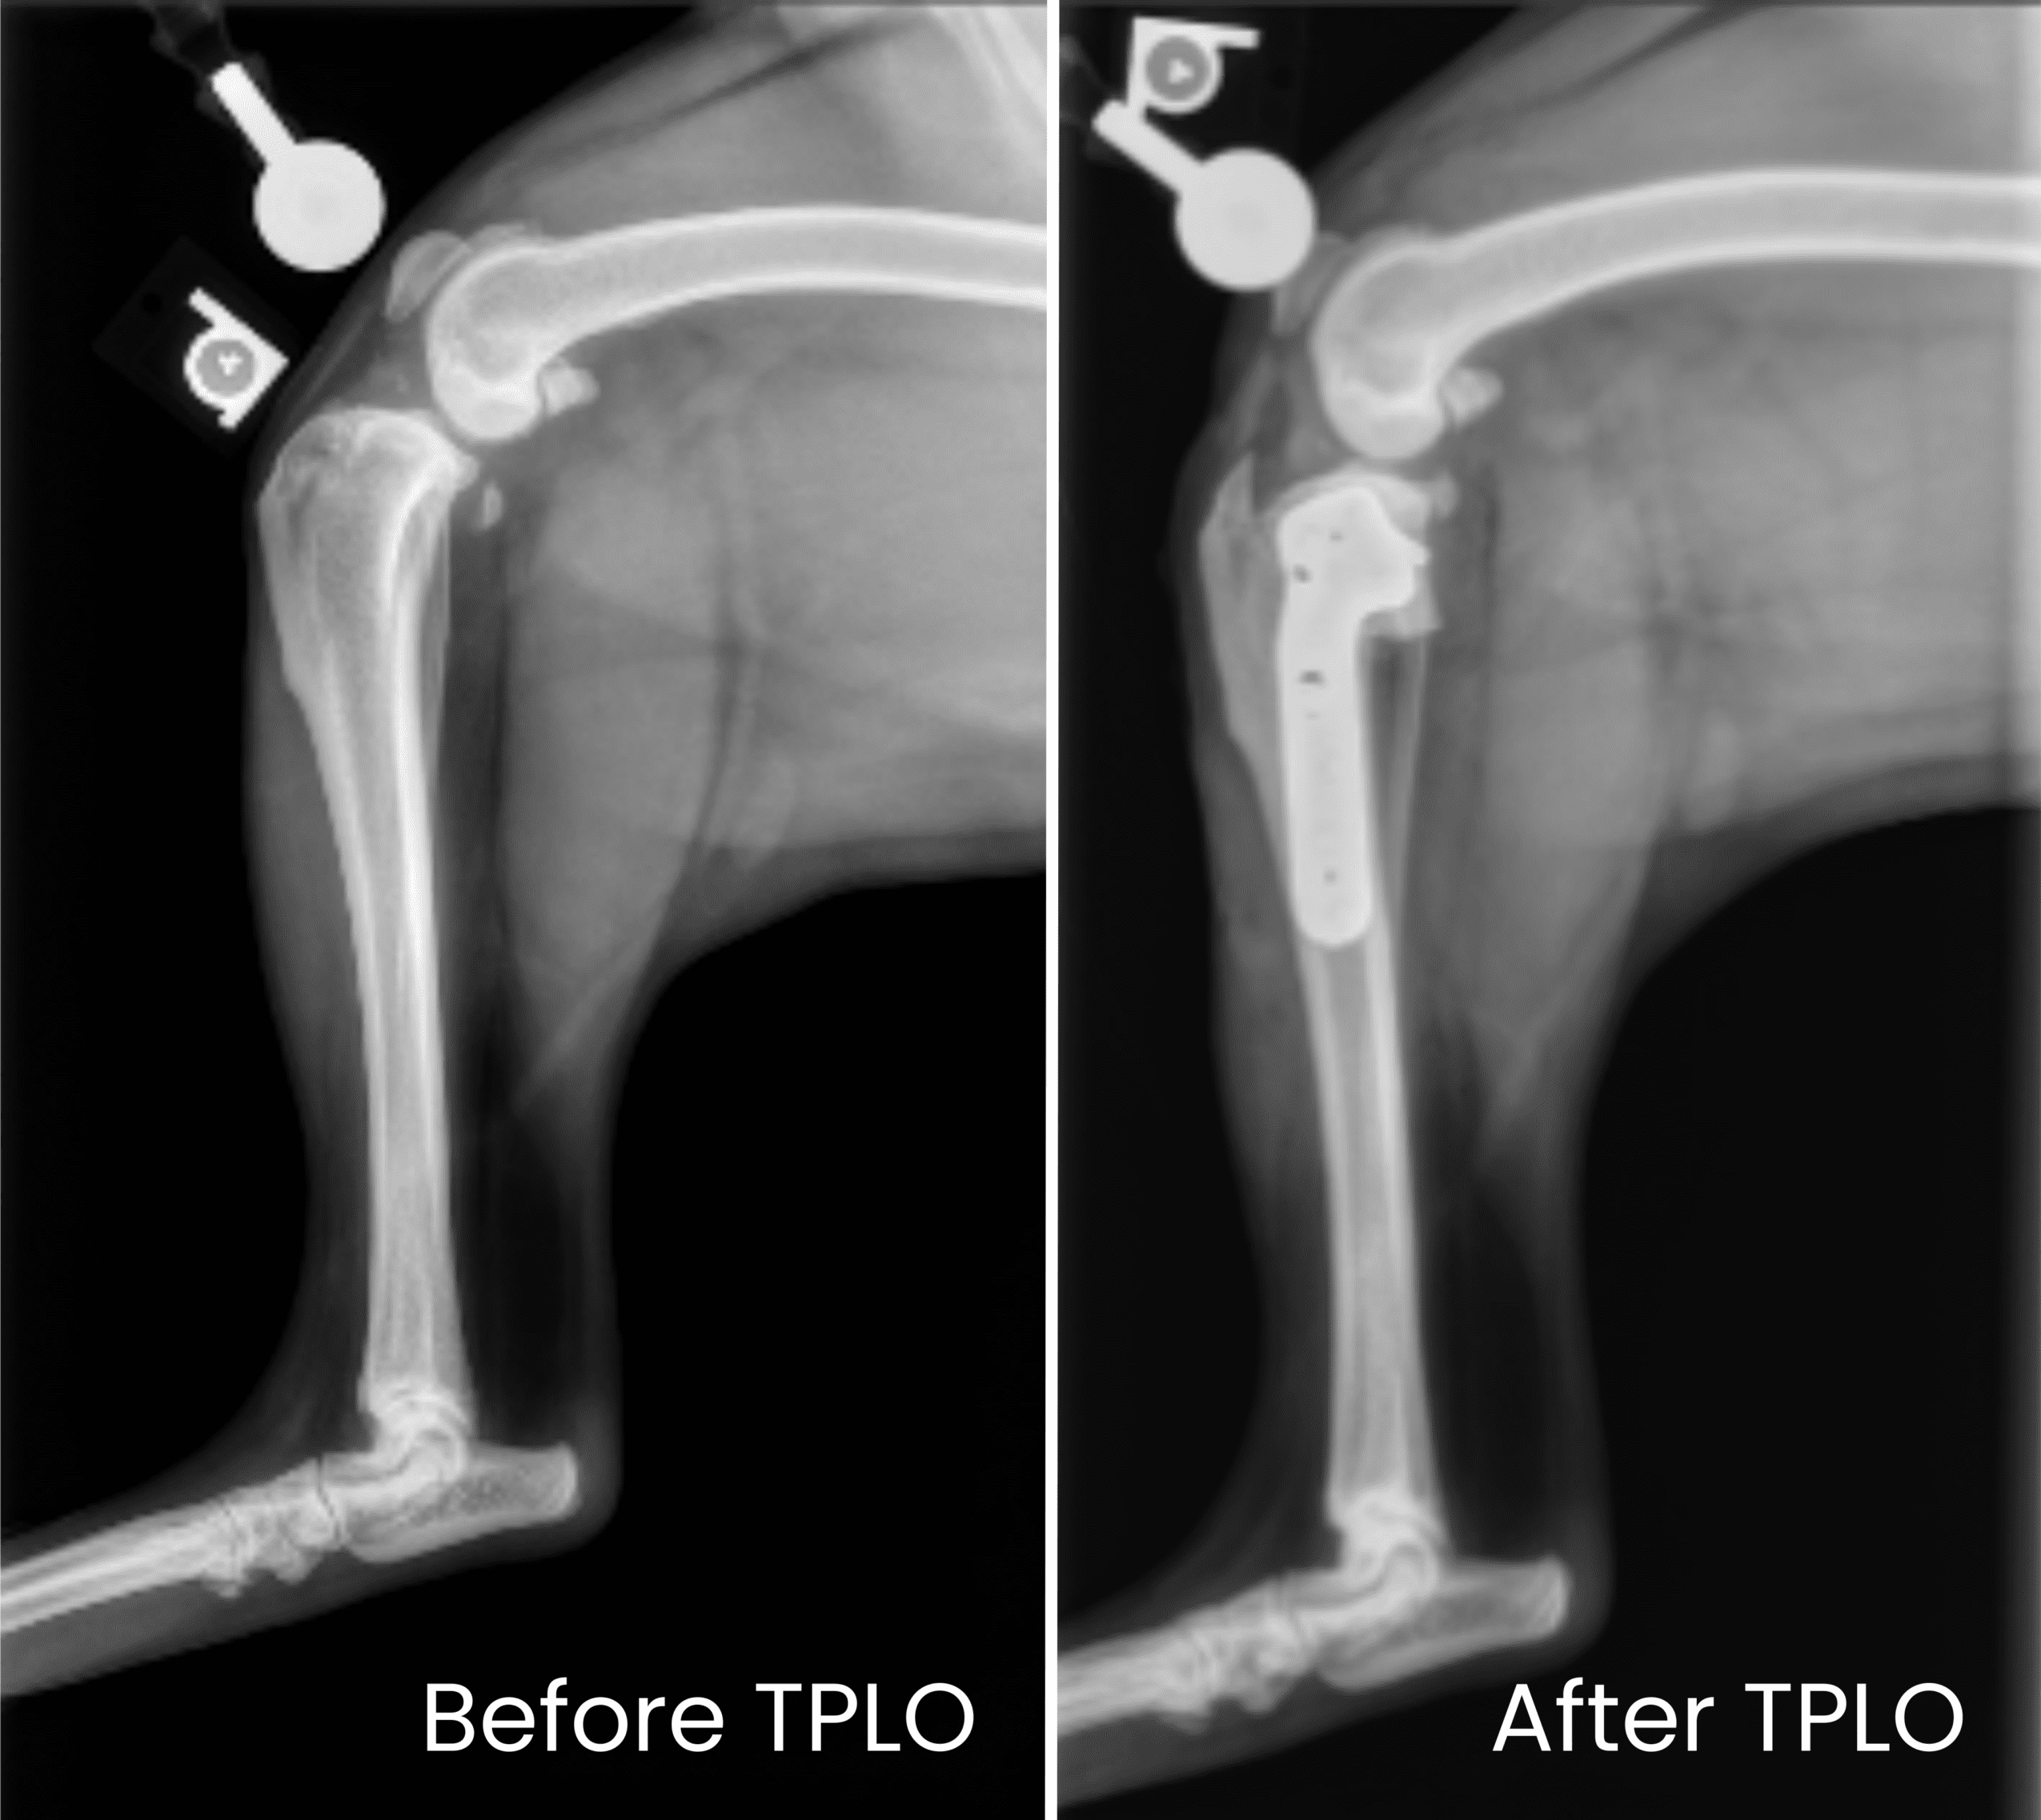

The procedure involves cutting and rotating the tibial plateau to change the slope of the knee joint. A metal plate and screws are used to secure the new angle, allowing for stable movement and healing.